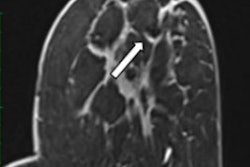

Nonvoluntary movement artifact. Axial turbo spin echo, T2-weighted slice of the thorax with multiple replicas of the aorta (arrows) displayed on the phase-encoding direction, due to the vibration. The best strategy here is to invert phase and frequency directions in case of periodic artifacts. All images courtesy of Dr. Patricia Andrea Gutierrez et al and presented at ECR 2023.Artifacts are defined as any part of an image that does not coincide with reality, according to the authors. They generate noise, cause distortion, and degrade image quality, and may have an impact on patient care. They can be classified as tissue, movement, or technical artifact, and they are numerous and multifactorial (e.g., magnet strength, objects in the room, Faraday cage effect, body part, physiology, and clinical state of the patient).